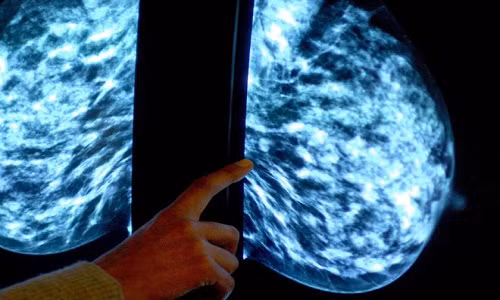

| 70% phụ nữ bị ung thư vú giai đoạn đầu có thể tránh sử dụng hóa trị. Ảnh: Independent. |